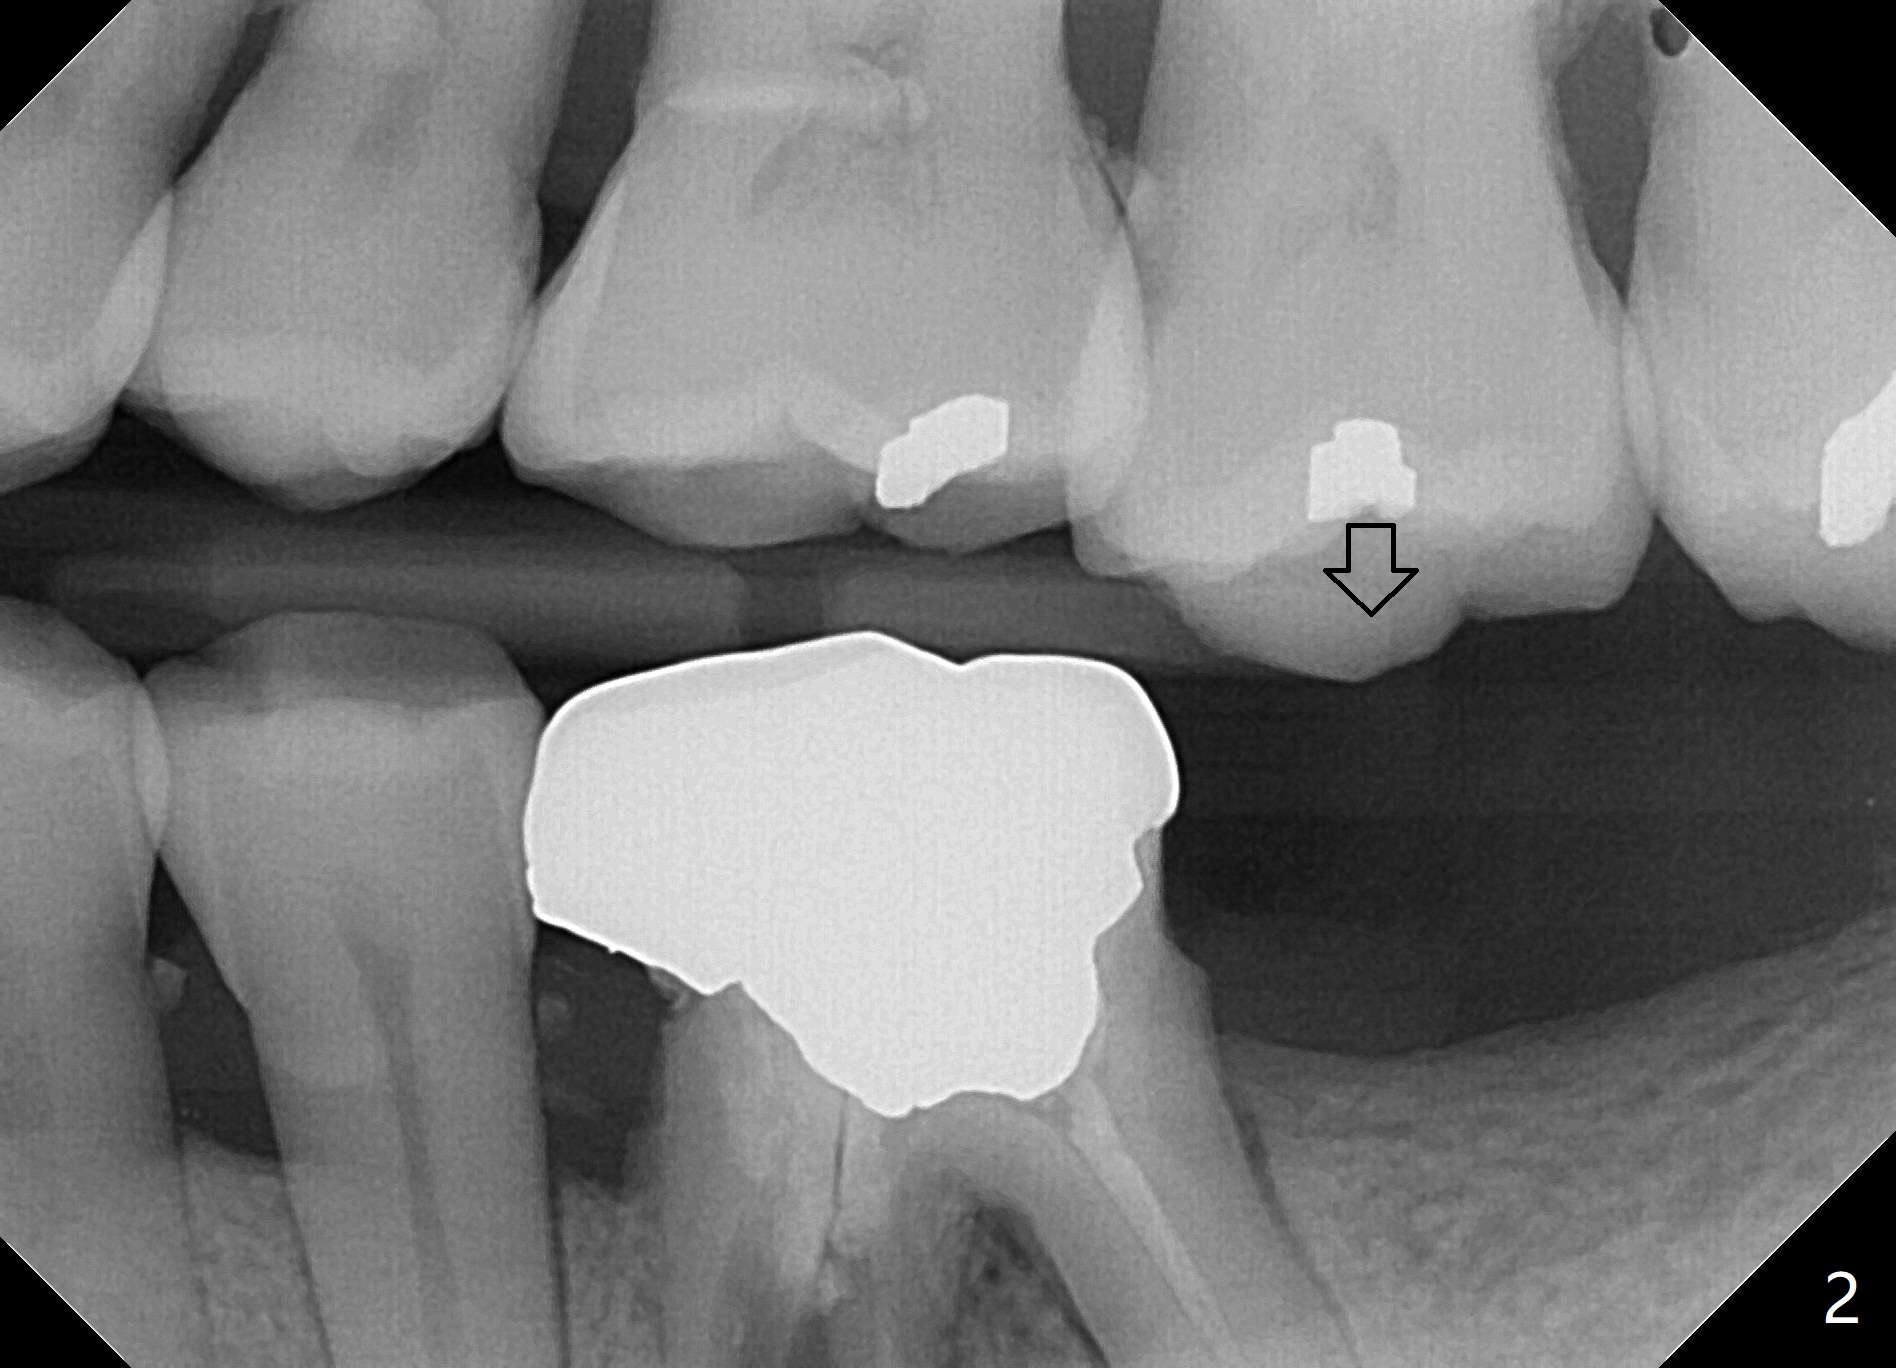

49岁男半年前要求粘固左下6牙冠,近中根纵裂,与7缺失有关,前磨牙牙根特别长,说明咬合力大,也是纵裂原因。最近他回来因为右下6远中舌侧牙尖折裂,全面X-ray检查显示左上7延长(图二:箭头),所以第二磨牙缺失是口腔修复物容易失败原因之一,影响口腔功能很大,很难修复。